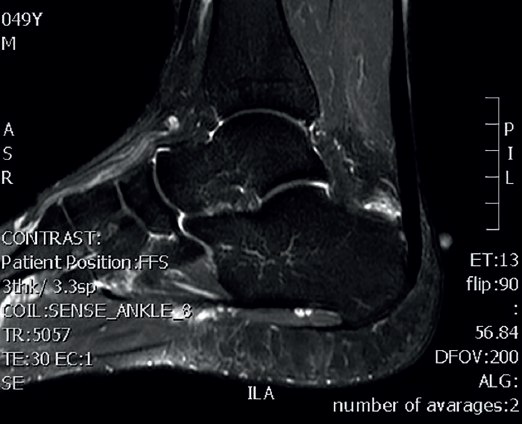

Magnetic resonance imaging (MRI) allows us to evaluate the presence of intratendinous injuries, fluid collections, the appearance of the bursae, bone edemas in the posterior tuberosity, and to establish the differential diagnosis with other disease conditions(22)(Figure 5). If the plain radiographs and ultrasound findings are conclusive, MRI is not essential. In the absence of an experienced ultrasound operator, or if there are doubts after ultrasound regarding the presence of disease in the tendon and bursa, MRI is very useful.

Figure 5. Magnetic resonance imaging. Retrocalcaneal bursitis. Fluid in the retrocalcaneal recess without signs of degenerative tendinopathy.